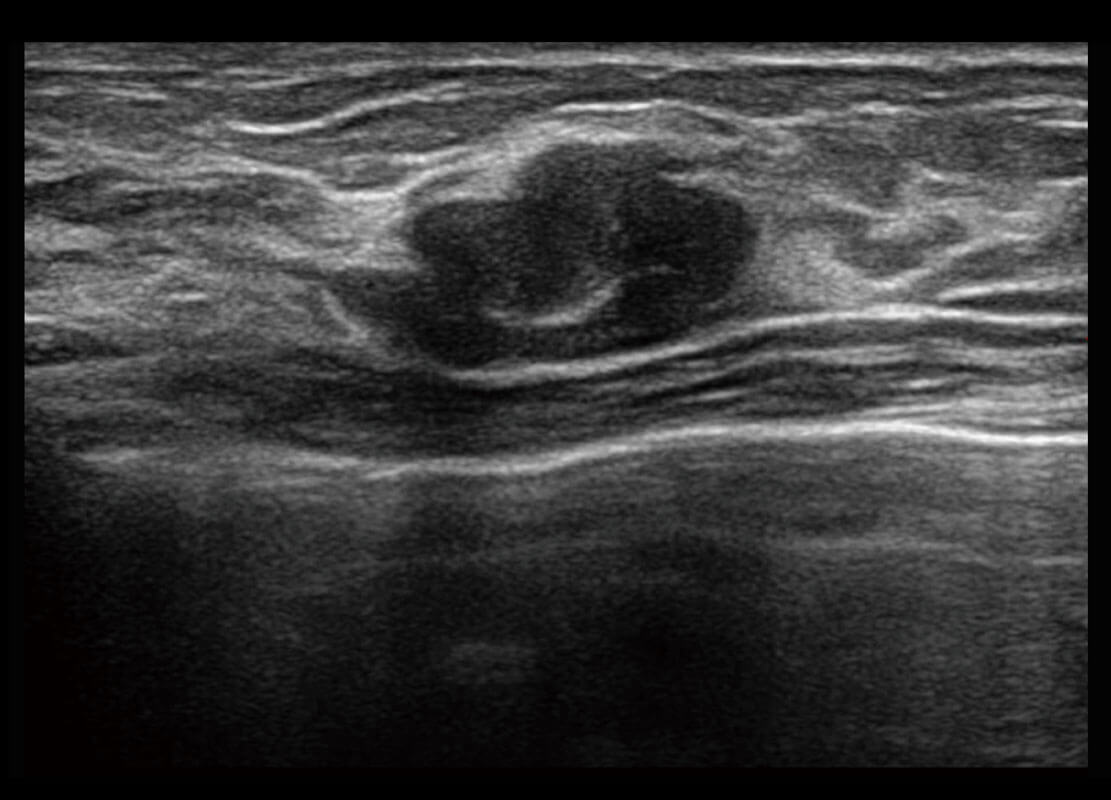

乳腺超声 / 新生儿

P60搭载宽频带线阵探头、宽景成像、弹性成像技术,为您提供乳腺应用方案。P60支持高频相控阵探头、线阵探头、腹部高频探头、腹部微凸探头等,丰富的探头群搭载敏感的彩色血流成像,适用于新生儿多种脏器检测要求,满足新生儿筛查需求。

• 乳腺导管癌

• 乳腺癌显微血流